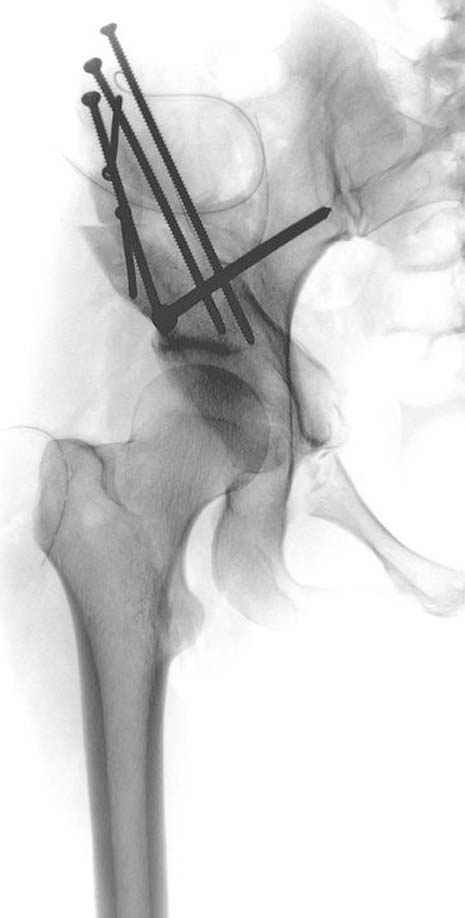

после операции при дисплазии тазобедренного

сустава #4

сустава #5

сустава #6

№ 1-3 до операции

№ 4-6 после операции при дисплазии тазобедренного

сустава

№ 11-12 послеоперационные, с учетом биомеханики